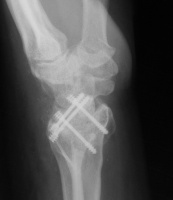

Radioscapholunate fusion is a treatment option for radiocarpal arthritis following distal radius fracture or associated with rheumatoid arthritis. Range of motion is usually less than half of normal following this procedure. Technical modifications to improve range of motion include distal scaphoid excision, or as in this case, triquetrum excision and excision of distal ulnar articular surface to manage ulnolunate abutment. There are a variety of fixation techniques. In this case, crossed Herbert screws were used: dorsal carpal bone to palmar radius and dorsal radius to palmar carpal bone.

Three months postop :

Image Image Image